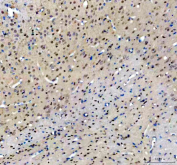

IHC staining of FFPE mouse brain tissue with NFIA antibody, HRP-secondary and DAB substrate. HIER: boil tissue sections in pH8 EDTA for 20 min and allow to cool before testing.

IHC staining of FFPE rat brain tissue with NFIA antibody, HRP-secondary and DAB substrate. HIER: boil tissue sections in pH8 EDTA for 20 min and allow to cool before testing.